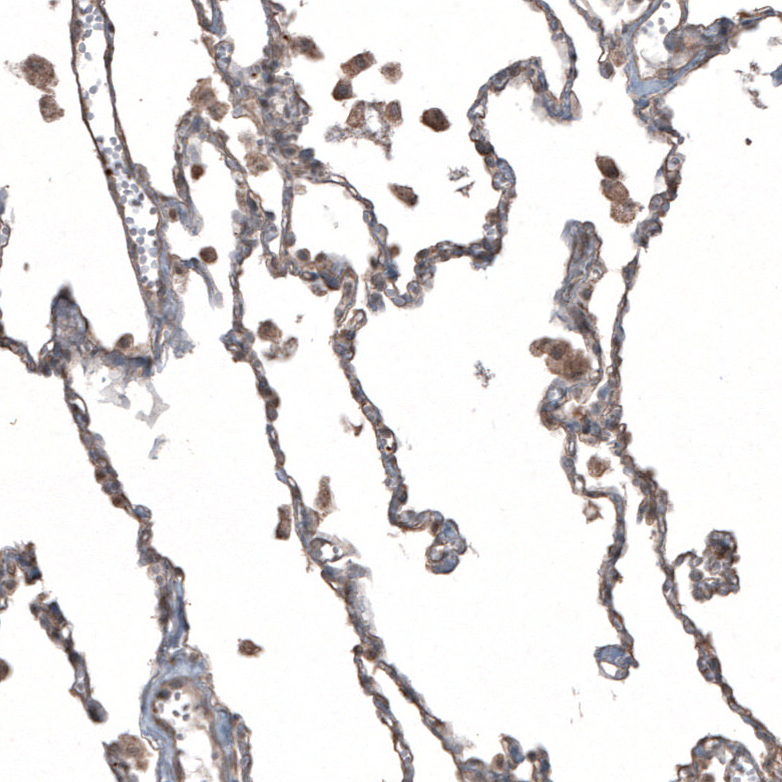

Immunohistochemical staining of human bone marrow shows moderate cytoplasmic positivity in hematopoietic cells.